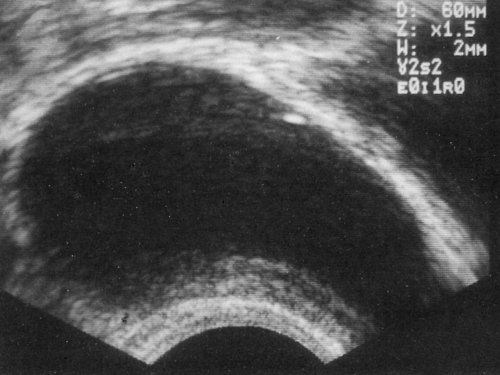

С помощью ТРУЗИ у 73 больных было обнаружено 118 кист (см. табл.). Из них только 10 врожденных кист (8,47%) у девятерых больных, включая пять кист предстательной маточки (рис. 1), три кисты парамезонефрического (мюллерова) протока (рис. 2,3), одну врожденную кисту семенного пузырька (рис. 4) и одну кисту семявыбрасывающего протока. Большинство кист предстательной железы были приобретенными [108 кист (91,53%) у 63 больных], включая 99 доброкачественных кистозных гиперплазии (рис. 5-7), восемь ретенционных кист (рис. 8) и один кистозный рак (рис. 9) - см. ниже. Киста наибольшего размера составляла 45 мм в диаметре, а наименьшая лишь 3 мм на сканограммах ТРУЗИ высокого разрешения.

На поперечном (а) и сагиттальном (б) срезах видна маленькая киста срединной линии.